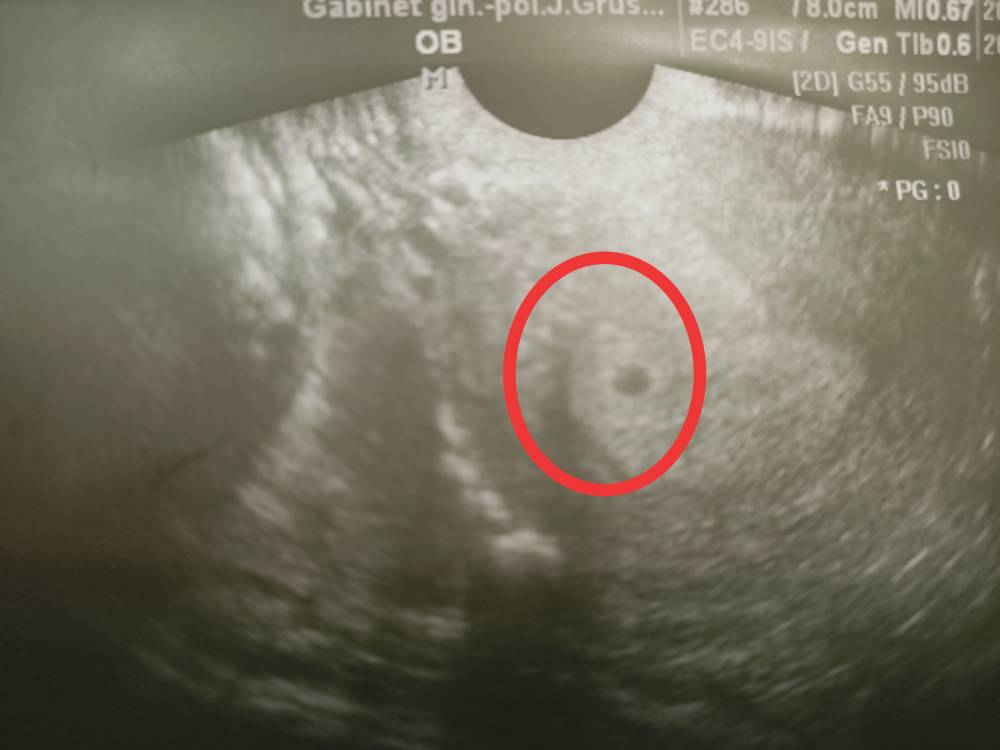

Jest pęcherzyk.

A tu poniżej przedstawiam swój pęcherzyk.Zobacz załącznik 1197211Zobacz załącznik 1197212